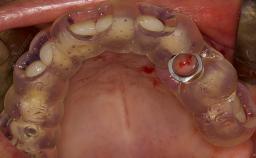

- postoperative complications of sinus floor elevation